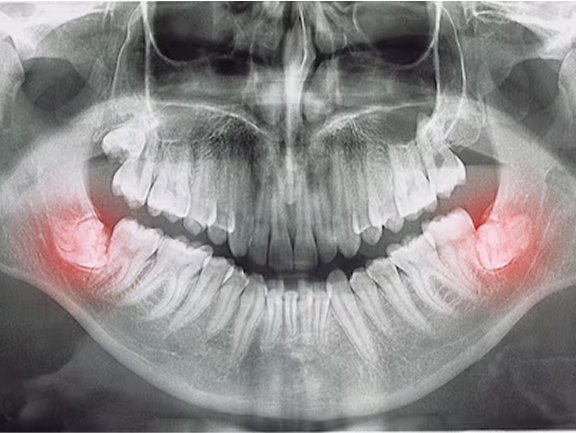

Impacted teeth

Sometimes adult teeth don’t emerge on schedule because they are blocked by other teeth in a crowded young mouth. Expansion widens the space available for adult teeth to erupt without interference.